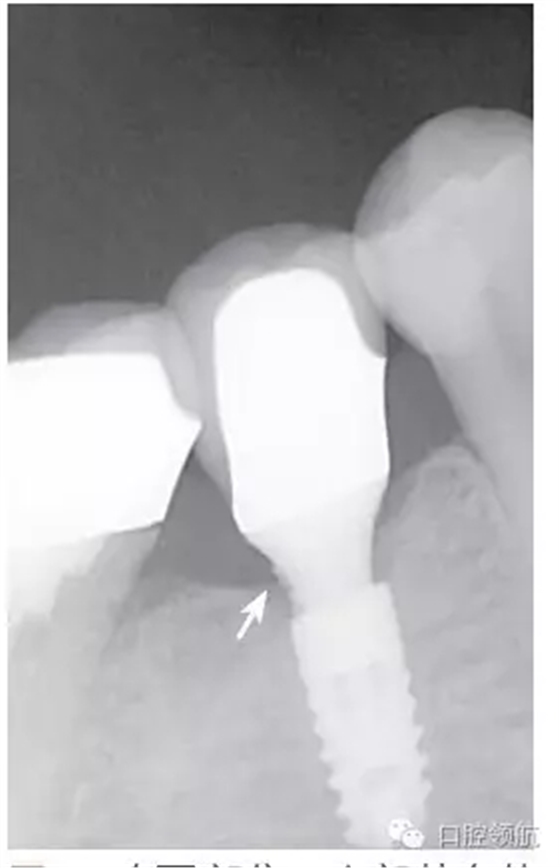

種植體的基臺(tái)與上部修復(fù)體的密合性,通過(guò)口腔X線片進(jìn)行檢查,確認(rèn)種植體周圍有殘留的粘接劑(圖2),使用探針等器械盡力清除剩余粘接劑,避免預(yù)后不良因素的產(chǎn)生。然后,通過(guò)X線片從投照的方向檢查確認(rèn)剩余的粘接劑,完全沒(méi)有殘留粘接劑的實(shí)際狀態(tài)(圖3)。

圖2 在(左下第五顆牙)部位,上部基臺(tái)的遠(yuǎn)中鄰面區(qū)域,看到了殘留的剩余粘接劑。